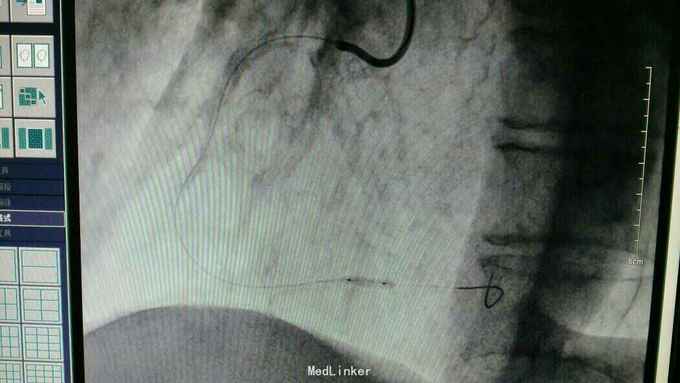

急性下壁心肌梗死,立即启动绿色通道,行急诊冠脉造影明确冠脉病变,必要时PCI治疗,行CAG示:LAD中重度狭窄,LCX尚可,RCA中段局限重度,可见前向血流,选段后降支处重度狭窄,血管钙化明显。考虑此次靶血管为RCA中段处,血管钙化迂曲明显,拟处理RCA,术中导丝到达远端后,预扩球囊反复高压扩张后,支架均无法通过,采用双导丝增加支撑依然无法通过,再更换高压后扩球囊高压扩张,锚定等,最终成功植入支架

急性心梗有时候处理相对较容易,但此病变在于血管钙化迂曲明显,且再次详细阅片后发现局部有“礁石”样病变,预扩球囊及后扩球囊不易扩张,有时需切割或旋磨,但对于急性心梗,如果血流达到理想级别,可不勉强处理,急性心梗中,有些病变为固定狭窄基础上急性血管闭塞,处理并非如一般血栓病变那样容易,造影后仍然需要详细阅片,根据具体病变情况选择合适手术处理方法